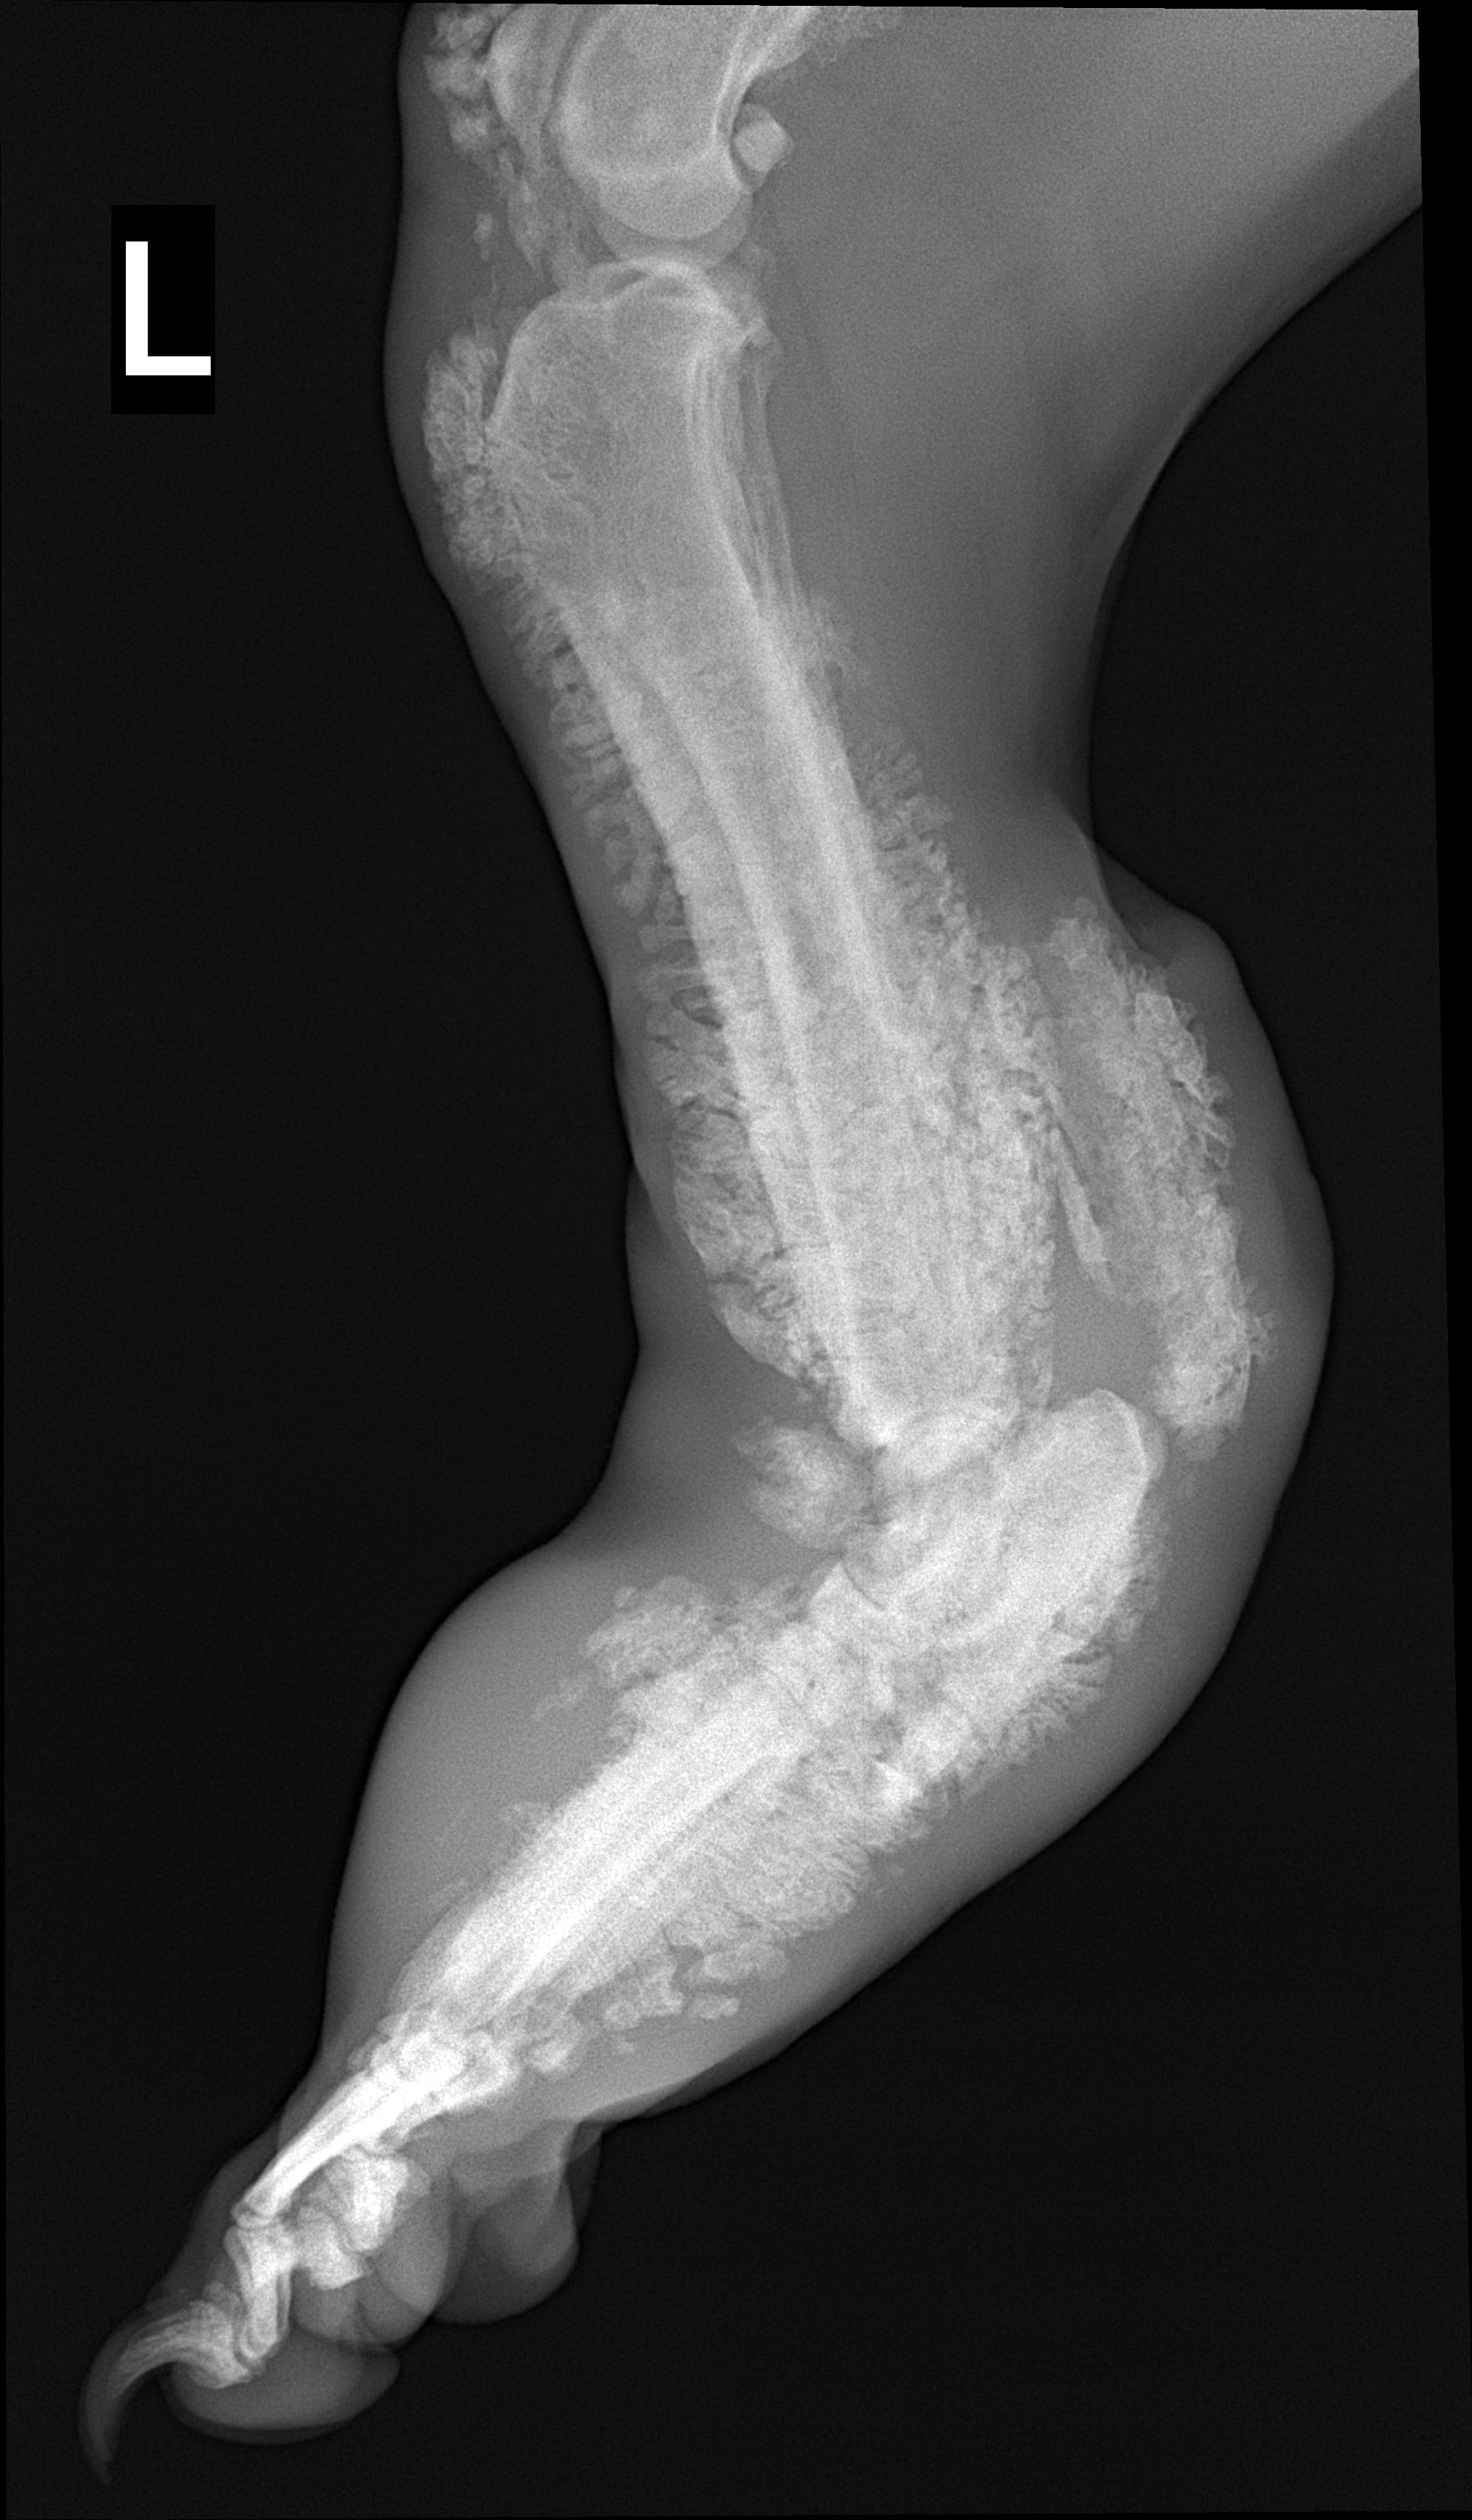

Species: Dog

Specimen: Radiograph

Shown: Hypertrophic osteopathy (Marie's disease) in pulmonary neoplasia